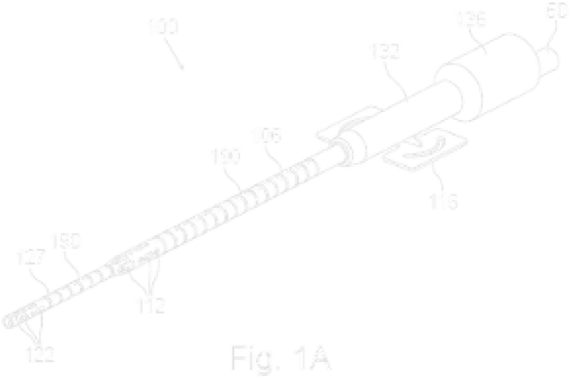

Dual Lumen Cannula

16 Novel Claims

The proprietary Convertible Dual Lumen Cannula is uniquely designed to offer multiple uses with intravascularly converting from a single-lumen cannula into a dual-lumen cannula after initial insertion. The unique cannula may potentially allow for fast action and reduced risk, complications and additional infection points.

An essential tool in a wide range of medical settings

A dual-lumen cannula is often used for the simultaneous venous drainage and reinfusion of blood during processes such Extra-Corporeal Membrane Oxygenation (ECMO) in Intensive Care Units (ICUs).

An essential tool in a wide range of medical settings

A dual-lumen cannula is often used for the simultaneous venous drainage and reinfusion of blood during processes such Extra-Corporeal Membrane Oxygenation (ECMO) in Intensive Care Units (ICUs).

Dual lumen cannula

- Granted in the U.S., 2023*

- Granted in the U.S., 2023

- Filed in Europe, China, Korea, Japan, Israel

A cannula fixation device

- Granted in the U.S. 2024

- Granted in Israel, 2022